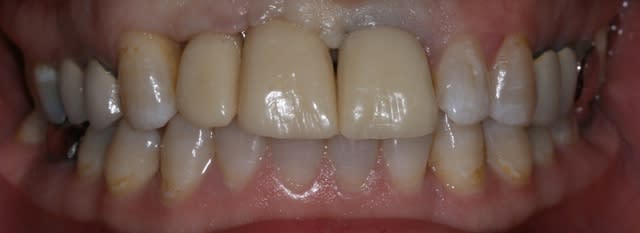

Bon finalement je vous poste le cas terminé.

La prochaine fois je ferrai une greffe d'apposition comme j'avais pu le préssentir... Ca me permettra de garder les papilles.

A la prochaine séance je gomme la coloration mésiale de 12, c'est promis ;+)

Un cas pas évident... l'important est que la patiente soit contente à la fin.

Dommage pour la teinte...

Une greffe osseuse aurait bcp aider, les implants sont trop enfouis par rapport à la 21.

Je suis persuadé que si ton prothèsiste réussit à reproduire la richesse des petits défauts de ses propres dents sur tes dents en céramique , ce serait et ça passerait bcp mieux

Je crois que finalement ces trois trop jaune et quasi monolithique ds leur couleur est vraiment la chose la plus atroce

Mon DuDule quel dommage que tu n'ai pas un ditramax car ta ligne interincisive n'est pas parallèle au plan médian et la ligne des bords libres pas parallèle à la ligne blanche masquant les yeux!

Sinon chirurgicalement c'est sympa compte tenu du terrain initial